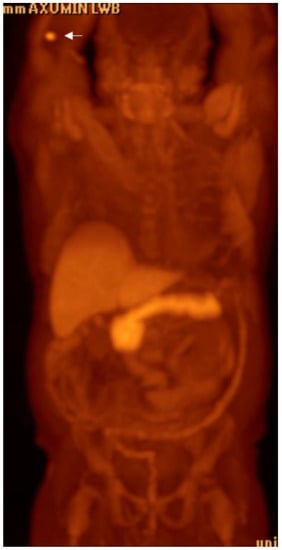

- At our institution, the reconstruction of fused maximum intensity projections (MIPs) are obtained in the coronal and sagittal planes, both of the entire body (vertex to knees) and of a narrow field-of-view of the pelvis.

Detection of Loco-Regional Disease and Distant Metastases